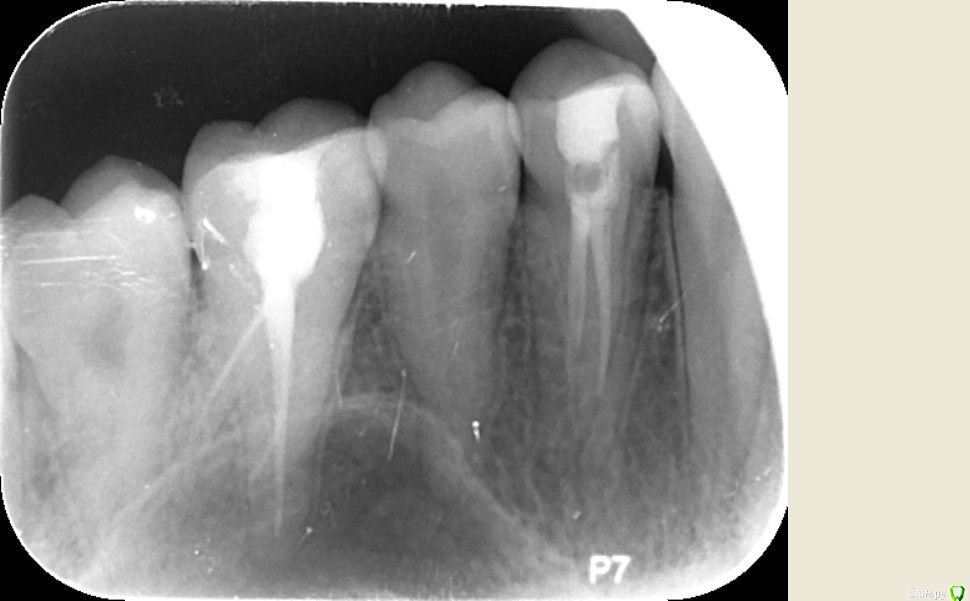

Nitrino1 Опубликовано 26 августа, 2016 Поделиться Опубликовано 26 августа, 2016 Уважаемые коллеги прошу у вас помощи так как сам не смог разобраться с данным случаем. Значит ситуация такая, приходила ко мне пациентка 3 месяца назад. Жалобы на боль слева сверху. Конкретно не знает какой зуб. Из анамнеза, боль появилась приблизительно год назад. Пошла к одному стоматологу, тот депульпировал 24-й заявляя что причина в нём. Боль не прошла. Пошли к другому стоматологу, тот заподозрил 26, депульпировал его. Боль не прошла. Пошли к третьему стоматологу, тот сказал что 24-й не правильно вылечен и "перелечил". Боль не прошла. Я четвёртый к кому они обращаются.Что имеем объективно. Пломбы на контактных пунктах нет. Десна была немного изменена в цвете в области сосочков между 24-25-26. При нажатии на десну небольшая боль. Перкуссия болезненная 24 и 26. Положил анестетик на десну - боль прошла. Заподозрил гингивит. Назначил лечение, флос, правильную чистку щеткой, Метрогил Дента на десну, Полоскание хлоргекседином и витамин общий. Боль прошла. Через неделю появилась, сделал в 3 посещения пасту из антибиотика и витамина А. Боль прошла на 2 месяца. Пришли ко мне недели 3 назад, те же самые боли. Перкуссия болезненна была на 24 в первое посещение. Во второе посещение болезенны были и 24 и 26. Промыл под сосочками хлоргексидином, назначил опять Метрогил Дента, полоскание хлоргекседином, правильную чистку. Прошла неделя, боли продолжаются. Помогите советами, что я упустил? Панораму сделал, там ничего такого. 24 и 26 вылечены не качественно и сам вижу, 24 даже в большей степени, но лечение десен же помогло, значит проблема в десне, а причину не могу определить. Ссылка на комментарий

сирена Опубликовано 26 августа, 2016 Поделиться Опубликовано 26 августа, 2016 На обоих зубах очаги,чё тут думать?Мазилки помогли не благодаря,а вопреки.Может,рефлекторное воздействие или самовнушение.Я так полагаю. 1 Ссылка на комментарий

DmitrySH Опубликовано 26 августа, 2016 Поделиться Опубликовано 26 августа, 2016 На обоих зубах очаги,чё тут думать?Мазилки помогли не благодаря,а вопреки.Может,рефлекторное воздействие или самовнушение.Я так полагаю. Поддерживаю. Если трудности с диагностикой, то лучше начать с очевидных вещей. В данном случае ревизия каналов точно нужна. Ссылка на комментарий

Nitrino1 Опубликовано 27 августа, 2016 Автор Поделиться Опубликовано 27 августа, 2016 Коллеги я с Вами согласен, сам так же хотел с перелечки начать, но напрягает два факта: боли начались до того как ей депульпировали два этих зуба и второй фактор - переходная складка не болезненная + после лечения десен 2 месяца болей не было + ей антибиотики назаначали перорально, а они как известно купируют хронический периодонтит, так вот, они ей вообще не помогли. Думаете все равно причина в 24 и 26? 28-ой я посмотрел сразу же, он прорезался но не полностью, в той области пальпация безболезненна, перкусия 27 тоже безболезненна. На 28 очагов кариеса нет Ссылка на комментарий